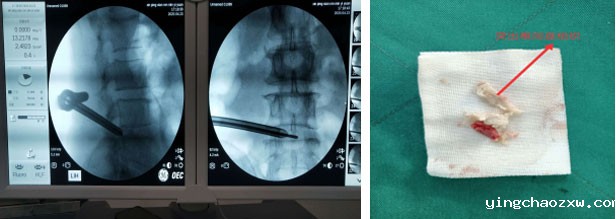

主要收治骨外科、神经外科、创伤外科、烧伤外科、血管外科患者,先后开展人工髋关节置换术、膝关节置换术、人工肩关节置换术、人工膝关节单髁置换术、髋关节感染病灶清除Spaecr植入术、下肢深静脉栓塞滤器植入术、下肢深静脉栓塞经皮导管溶栓术、膝关节关节镜下清理、半月板缝合、交叉韧带重建术、脊柱内镜下椎间盘摘除术、颈腰椎间盘突出椎管减压融合术,腰椎管狭窄、腰椎滑脱椎管减压术、融合术,脊柱骨折内固定术、椎体成形术(PKP、PVP)等多项现代医疗技术及骨盆骨折、四肢创伤骨折、脱位等手术。近年来,外二科各项现代医疗技术不断涌现,先后开展了外周血管介入手术、椎间孔镜下椎间盘摘除术、(MIS-TLIF)微创椎间融合术治疗腰椎间盘突出症、神经介入手术、脑出血微创治疗、脑膜瘤切除术等新技术。

椎间孔镜下椎间盘摘除术